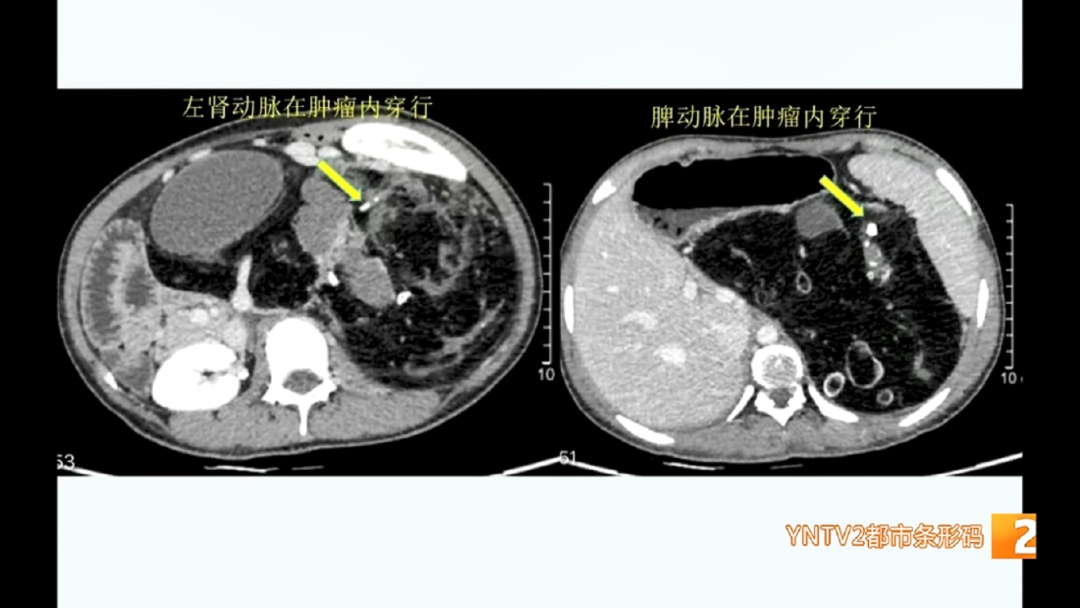

这个直径超过50厘米的肿瘤犹如一个“定时炸弹”,持续压迫患者的胃肠、胰腺等重要脏器,甚至将左肾动脉和脾血管系统完全包围,后期还会有癌变的可能。

云南省第三人民医院 肝胆胰外科主治医生 陈伟:“左肾动脉和脾动脉在肿瘤内穿行,最坏的结果是肿瘤切除了,左肾脏和脾脏可能保不住,后期我们也和家属沟通,如果他们能接受这个结果,我们肯定能保证将肿瘤切除。”